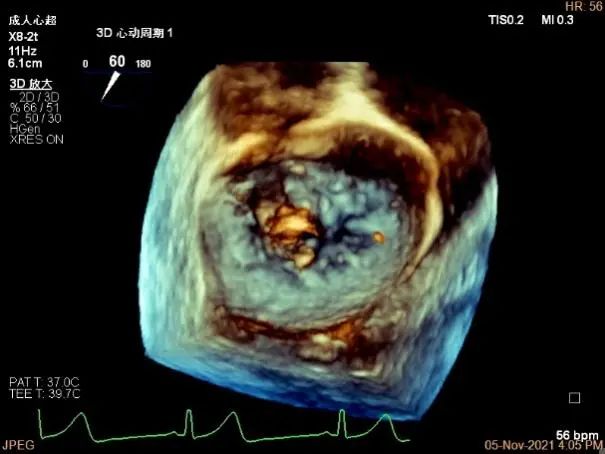

3D MV View:A2/A1区脱垂

A2P2区前后叶长度可,为主要脱垂区域,进而制定手术策略: 2区一个长夹子解决脱垂主要病变区域

3D视图下观察二尖瓣双孔形态